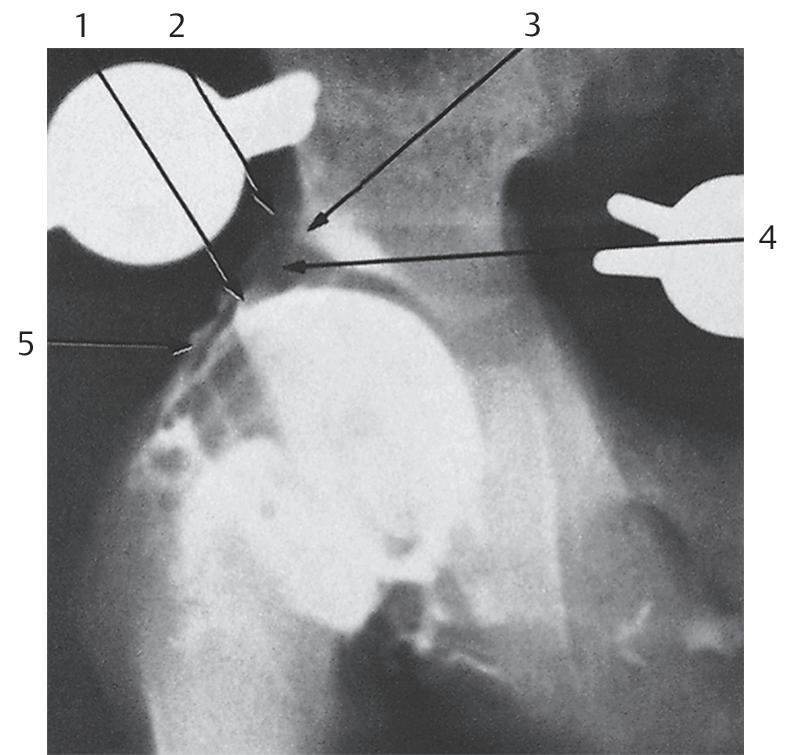

A artrografia, com a possibilidade de representar partes não ossificadas e tecidos moles da articulação do quadril, aproxima-se bastante das possibilidades da ultrassonografia do quadril ( ▶ Fig. 1.2). No entanto, a artrografia do quadril foi amplamente substituída pela ultrassonografia do quadril. Mesmo assim, o diagnóstico artrográfico contribuiu significativamente para a compreensão da fisiopatologia do processo de luxação [12, 19, 67, 77, 88, 99].

Fig. 1.2 Artrografia do quadril direito. Preparação do cadáver.

1 = Lábio acetabular

2 = Pericôndrio

3 = Borda óssea

4 = Teto cartilaginoso

5 = Cápsula articular